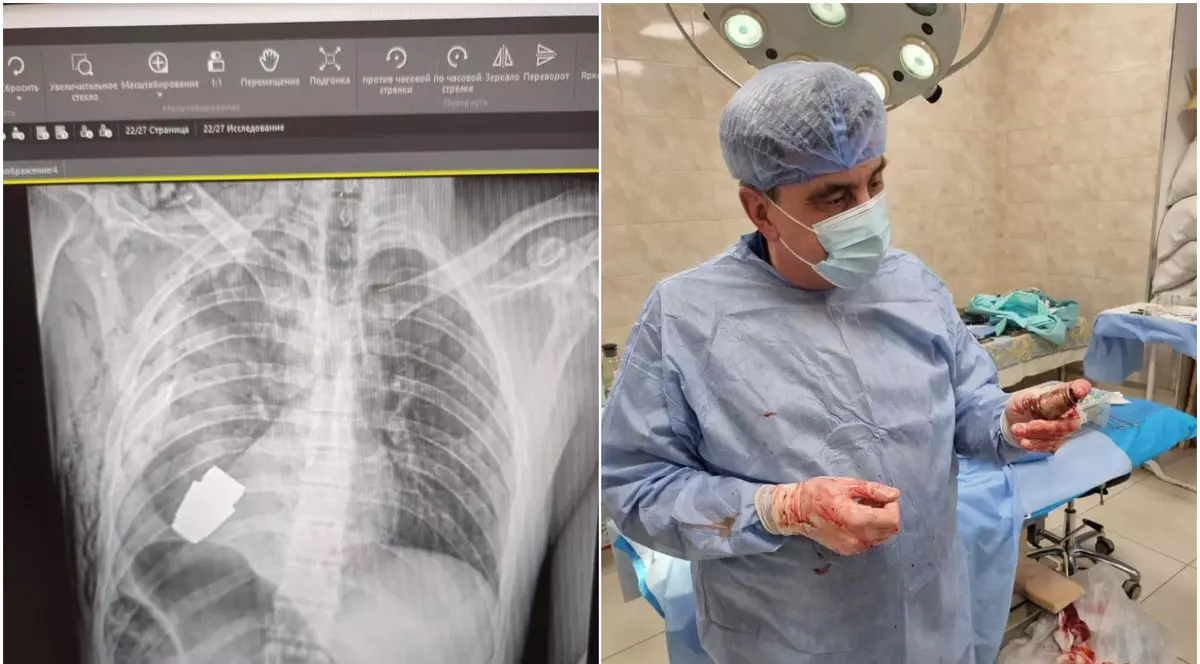

„Medicii noștri militari au efectuat o intervenție chirurgicală pentru a îndepărta o grenadă VOG neexplodată din corpul unui soldat. Operația a fost realizată în prezența a doi geniști care au supravegheat siguranța personalului medical și a pacientului”, a precizat conducerea armatei ucrainene, în postare, alături de o radiografie și de o fotografie cu proiectul scos din corpul militarului.

„Unul dintre cei mai experimentați chirurgi ai Forțelor Armate, generalul-maior Andrew Willow, a operat fără electrocoagulare, întrucât grenada putea exploda în orice moment”, a adăugat Statul Major General.

Potrivit Comandamentului Forțelor Medicale al Forțelor Armate ale Ucrainei, intervenția chirurgicală a reușit, iar soldatul rănit a fost trimis să se recupereze, menționează sursa citată.